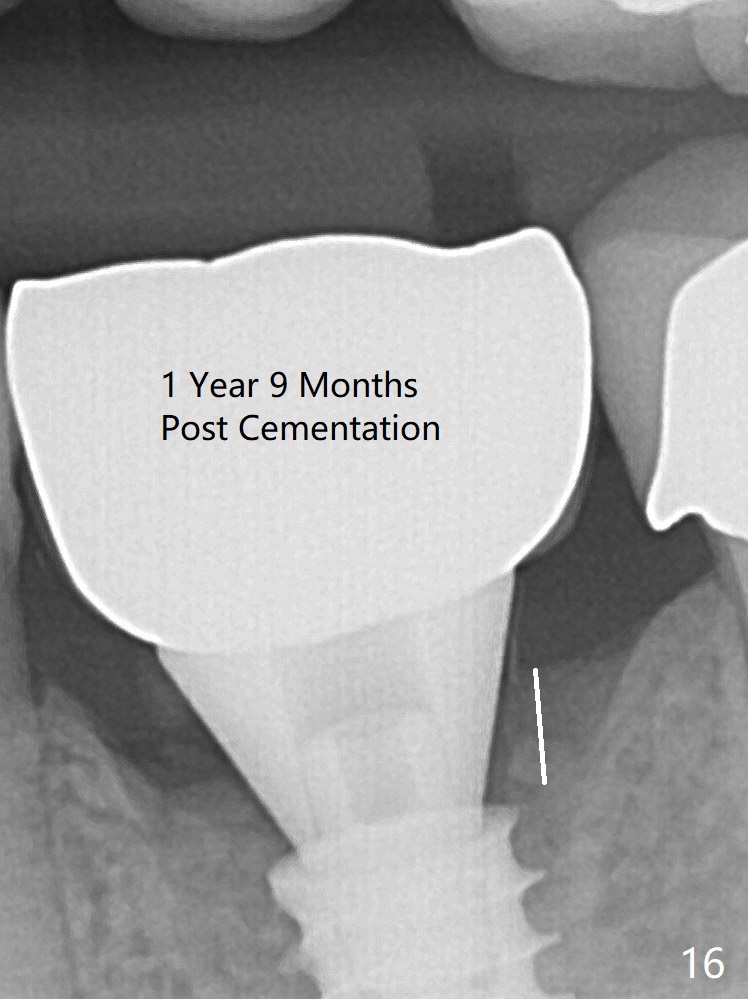

New bone has apparently covered the implant plateau 8 months postop (3 months post cementation (Fig.13 arrows)). The lower two-thirds of socket have disappeared. Bone density between threads increases 9 months post cementation (Fig.14). There is 2 mm bone superior to the implant plateau mesial and distal 1 year 9 months post cementation (Fig.15,16).